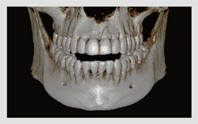

• 3D CT

치아, 잇몸뼈 골격까지 진단

• 정밀한 진단을 통한 체계적인 계획

치아뿌리 길이, 모양, 잇몸뼈의 두께와 밀도, 과잉치와 치아종 등 3D CT 정밀진단을 통해 환자의 치아 및 잇몸 상태를 고려한 치료계획을 세울 수 있습니다.